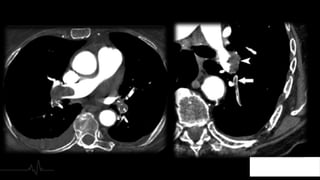

3. Extensión

4. AFECTACIÓN

PARENQUIMATOS

A● Inicialmente: Opacidad en vidrio

deslustrado, segmentaria, de morfología

triangular y base pleural.

● Con el paso del tiempo: Consolidación.

● Se puede identificar una atelectasia del

área afecta, la isquemia pulmonar provoca

una alteración del surfactante con colapso

secundario.

Imposibilidad de distribuir toda la

volemia de la circulación derecha al

pulmón, aumento de presión y aumento

de calibre de la arteria pulmonar.

Debe ser inferior al de la aorta

ascendente y debe medir menos de 3 cm

5. Hipertensión

Pulmonar

4. AFECTACIÓN PARENQUIMATOS A● Inicialmente:Opacidad en vidrio deslustrado, segmentaria, de morfología triangular y base pleural. ● Con el paso del tiempo: Consolidación. ● Se puede identificar una atelectasia del área afecta, la isquemia pulmonar provoca una alteración del surfactante con colapso secundario.

Imposibilidad de distribuirtoda la volemia de la circulación derecha al pulmón, aumento de presión y aumento de calibre de la arteria pulmonar. Debe ser inferior al de la aorta ascendente y debe medir menos de 3 cm 5. Hipertensión Pulmonar